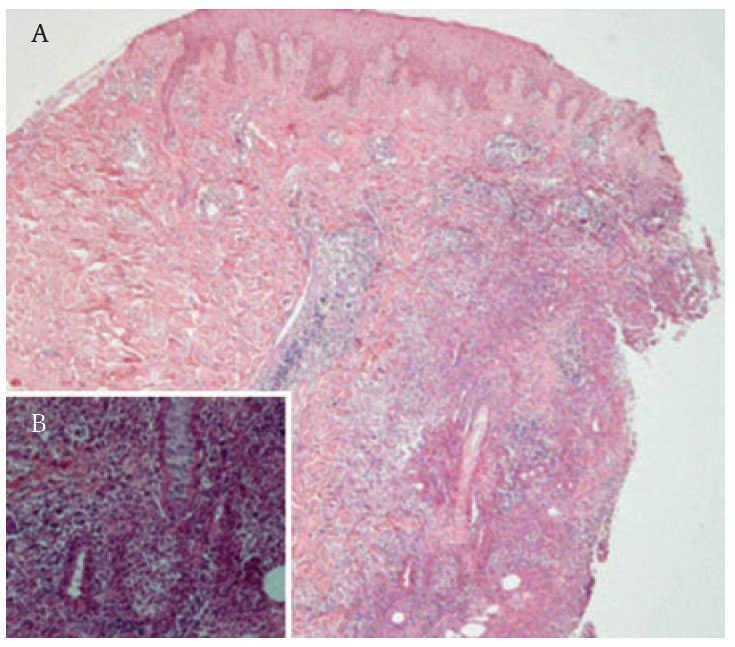

Reporte del casoSe trata de una mujer de 52 años con diagnóstico de CU de 10 años de evolución. Como única manifestación extraintestinal presentaba artritis periférica. Debido a la presencia de displasia de alto grado en biopsia obtenida por colonoscopia, fue sometida a una proctocolectomia con reservorio ileoanal e ileostomía en asa. El periodo posoperatorio de la paciente transcurrió sin complicaciones y se egresó a los cinco días. Seis semanas después de la cirugía, la paciente refirió un dolor intenso en el área periostomal. A la exploración se observó una gran úlcera que rodeaba el estoma con secreción purulenta y necrosis en los bordes (figura 1). Ésta se trató inicialmente como una falla en el manejo del estoma con dermatitis de contacto y una infección agregada. La paciente recibió tratamiento con antibióticos orales y capacitación en el manejo de estoma. Después de dos semanas, la lesión empeoró y apareció una nueva úlcera en la región escapular derecha de iguales características, pero más pequeña (figura 2). El diagnóstico se realizó por medio de una biopsia. En el estudio histopatológico de la piel periostomal se observó inflamación aguda y crónica en la dermis y en el tejido adiposo (HE-40X) (figura 2). También se observaron abscesos y vasculitis, así como migración de polimorfonucleares hacia la pared vascular (125X). Los cultivos de las biopsias no desarrollaron colonias. La paciente no tenía evidencia de enfermedad intestinal activa. El tratamiento se realizó con 40 mg al día de prednisona orales y con cuidados locales de la úlcera, incluyendo debridación bajo anestesia local. Las úlceras cicatrizaron a los seis meses de tratamiento y al año no presentó recurrencia.

Figura 2. Pioderma gangrenoso escapular.